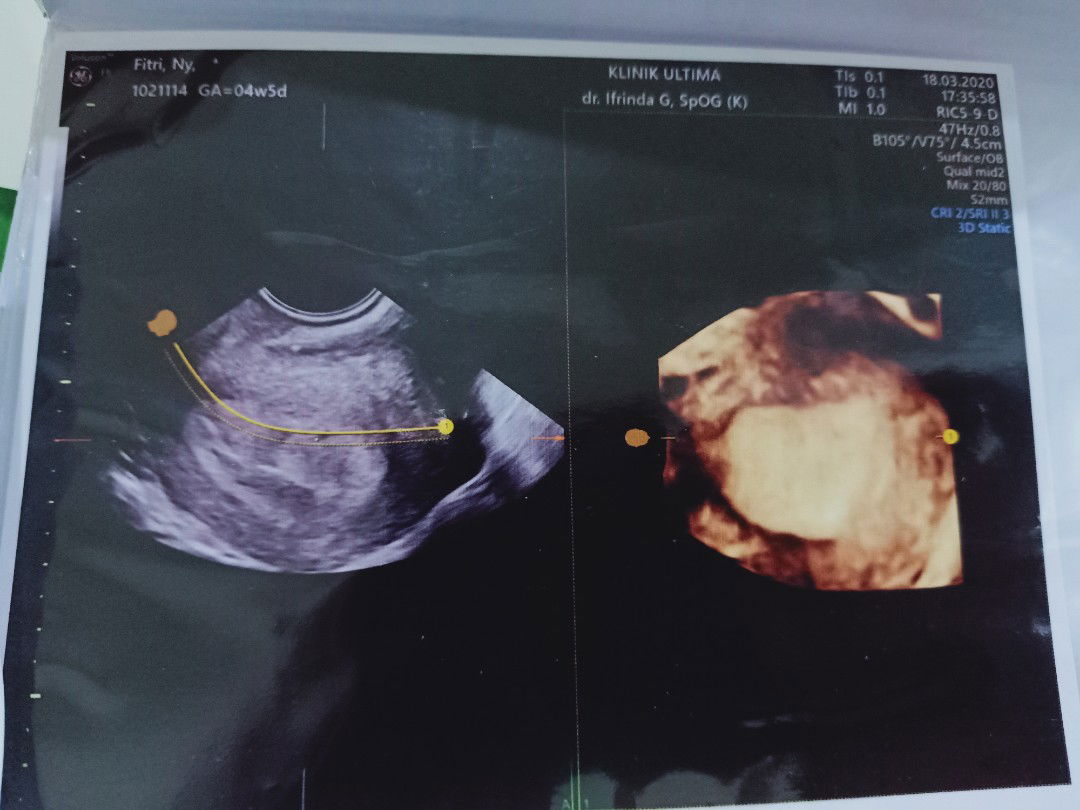

Hasil USG 4minggu

Semoga bunda berkenan berbagi pengalaman bagi saya yg sangat parno dikehamilan pertama saya ,Apakah normal Bun di usia kandungan 4minggu hanya terlihat kantung kandungan dan belum terlihat si embrio walaupun sudah USG 3D ,smoga pengalaman bunda bisa menambah ilmu bagi saya dan mengurangi kepanikan saya